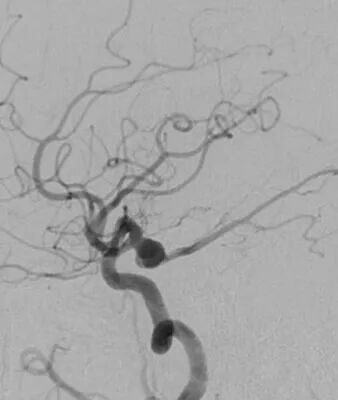

左侧后交通动脉瘤,胚胎型大脑后动脉

3D

局部观,宽颈,涉及颈内动脉和后交通动脉

椎动脉造影见左侧大脑后动脉P1段很细